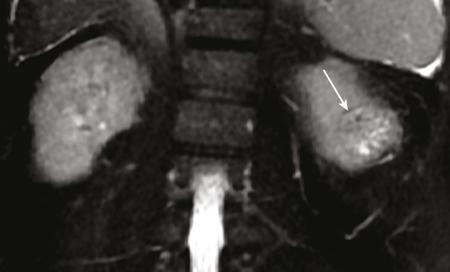

IMAGING OF RENAL MALIGNANCIES IN ADULTS Aparna Katdare, Palak Bhavesh Popat, Nilesh P. Sable, Ganesh Bakshi, Suyash Kulkarni Detection of renal masses has increased remarkably in recent times owing to wide-spread use of cross-sectional imaging. Imaging plays an important role in characterizing renal masses and is indispensable in treatment planning in renal malignancies. The most commonly encountered malignant renal masses in practice include renal cell carcinoma (RCC), urothelial carcinoma, lymphoma and metastases. Urothelial carcinoma and lymphoma have been covered in detail in separate chapters. RCC constitutes nearly 90% of all renal malignancies with a higher incidence in North America and Europe than India, Africa and China. With an increase in the number of cross-sectional studies performed, especially in Western population, the incidental diagnosis of RCC has increased in recent times, with such incidentally diagnosed lesions presenting at earlier stages with better prognosis and reduced rates of recurrence. The median age of presentation of RCC is 64 years according to the Surveillance, Epidemiology and End Results (SEER) program database and almost a decade earlier in Indian population, with a definite increasing risk of RCC with increasing age. Males are affected about 2–3.5 times more than females. In the Indian population, patients have been seen to present at a later stage as compared to the Western population. Amongst the various postulated risk factors, there is convincing evidence that smoking, hypertension, obesity and acquired renal cystic disease increase the risk of RCC. Alcohol intake and physical activity have been found to be associated with reduced risk of RCC. Trichloroethylene and cadmium exposure have been postulated as likely causes as well. Two to four per cent of RCCs are hereditary, with association of various genetic disorders such as Von Hippel Lindau (VHL) syndrome, hereditary papillary renal carcinoma, hereditary leiomyomatosis RCC, Birt-Hogg-Dube syndrome, chromosome 3 translocation and tuberous sclerosis (TCS1, TCS2). The WHO classification of 2016 (Table 11.25.1.1) stratifies tumours of the kidney into different subtypes based on cytoplasmic and architectural features, tumour location, background renal disease and molecular alterations. Clear cell renal cell carcinoma Multilocular cystic renal neoplasm of low malignant potential Papillary renal cell carcinoma Hereditary leiomyomatosis and renal cell carcinoma-associated renal cell carcinoma Chromophobe renal cell carcinoma Collecting duct carcinoma Renal medullary carcinoma MiT family translocation renal cell carcinomas Succinate dehydrogenase-deficient renal carcinoma Mucinous tubular and spindle cell carcinoma Tubulocystic renal cell carcinoma Acquired cystic disease-associated renal cell carcinoma Clear cell papillary renal cell carcinoma Renal cell carcinoma, unclassified Papillary adenoma Oncocytoma 8310/3 8316/1a 8260/3 8311/3* 8317/3 8319/3 8510/3a 8311/3a 8311/3 8480/3a 8316/3a 8316/3 8323/1 8312/3 8260/0 8290/0 Metanephric adenoma Metanephric adenofibroma Metanephric stromal tumour 8325/0 9013/0 8935/1 Nephrogenic rests Nephroblastoma Cystic partially differentiated nephroblastoma Paediatric cystic nephroma 8960/3 8959/1 8959/0 Clear cell sarcoma Rhabdoid tumour Congenital mesoblastic nephroma Ossifying renal tumour of infancy 8964/3 8963/3 8960/1 8967/0 Leiomyosarcoma Angiosarcoma Rhabdomyosarcoma Osteosarcoma Synovial sarcoma Ewing sarcoma Angiomyolipoma Epithelioid angiomyolipoma Leiomyoma Haemangioma Lymphangioma Haemangioblastoma Juxtaglomerular cell tumour Renomedullary interstitial cell tumour Schwannoma Solitary fibrous tumour 8890/3 9120/3 8900/3 9180/3 9040/3 9364/3 8860/0 8860/1a 8890/0 9120/0 9170/0 9161/1 8361/0 8966/0 9560/0 8815/1 Cystic nephroma Mixed epithelial and stromal tumour 8959/0 8959/0 Well-differentiated neuroendocrine tumour Large cell neuroendocrine carcinoma Small cell neuroendocrine carcinoma Phaeochromocytoma 8240/3 8013/3 8041/3 8700/0 Renal haematopoietic neoplasms Germ cell tumours The morphology codes are from the International Classification of Diseases for Oncology (ICD-O) {917A}, Behaviour is coded/0 for benign tumours; /1 for unspecified, borderline or uncertain behaviour; /2 for carcinoma in situ and grade III intraepithelial neoplasia; and /3 for malignant tumours. The classification is modified from the previous WHO classification (756A), taking into account changes in our understanding of these lesions. aNew code approved by the IARC/WHO Committee for ICD-O. Of these, the most common entity is the clear cell subtype, while papillary and chromophobe subtypes are less common. The different subtypes show varied biological behaviour, treatment response and prognosis. The 2017 guidelines by American Urological Association (AUA) as well as 2019 guidelines by European Society of Medical Oncology (ESMO) recommend multiphase cross-sectional imaging by either CT or MRI for renal mass characterization and staging. AUA 2017 guidelines recommend renal mass characterization on the basis of tumour complexity, contrast enhancement and presence or absence of fat. MRI has an upper hand over CT in characterizing subtle mass enhancement, cystic lesions and lesions less than 2 cm. ESMO recommends contrast-enhanced CT study of the chest, abdomen and pelvis for renal mass staging. Bone scan and brain CT or MRI can be considered if indicated by clinical or laboratory investigations. For characterization of renal masses, a multiphase CT or MRI study is recommended. CT study constitutes an unenhanced study followed by contrast injection and acquisition of corticomedullary phase at 40 seconds, nephrographic phase at around 100 seconds and delayed phase at around 5 minutes. MRI protocol includes T2-weighted single-shot fast spin-echo 2D sequences, axial T1-weighted 2D sequence with in-phase and opposed-phase gradient echo imaging, precontrast and postcontrast imaging with a 3D T1-weighted spoiled gradient recalled sequences in corticomedullary phase at 30 seconds, nephrographic phase at 100 seconds, 180–210 seconds and delayed phase imaging at 5 minutes and diffusion-weighted imaging with multiple b-values 0–50, 400–500 and 800–1000 s/mm2. The ACR White Paper on CT imaging of incidental renal mass recommends using the following descriptors for characterizing renal masses: Given the prognostic implications, it is worthwhile for radiologists to know the imaging features that may help discriminate between the common histological subtypes of RCC on various imaging modalities. This is the most common histological type of RCC, accounting for about 70% of cases. These are exophytic tumours with a heterogeneous appearance due to the presence of necrosis, intratumoural haemorrhage, cystic components with septations and calcific foci and hence have a more heterogeneous appearance on cross-sectional imaging than the other subtypes (Fig. 11.25.1.1). Necrosis is seen more often in larger masses and higher tumour grades (Fig. 11.25.1.2). On CT, depending on the tumour composition, these are seen as heterogeneous lesions, show marked contrast enhancement in the corticomedullary phase with washout on nephrogenic phase (Fig. 11.25.1.2). On MRI, these characteristically show high signal intensity on T2W sequences (Fig. 11.25.1.3). The presence of intracytoplasmic fat in the clear cells of the tumour is reflected in the loss of signal in opposed phase images on chemical shift imaging, which is seen in nearly 60% of these tumours. A pseudocapsule may be seen, which is best appreciated on T2-weighted imaging on MRI; the presence of a pseudocapsule has a high negative predictive value for perinephric extension (Figs. 11.25.1.3 and 11.25.1.4). Conversely, larger tumours with higher grades often have interrupted pseudocapsule and hence tend to be irregular, spread into the perinephric fat with renal vein and inferior vena cava (IVC) invasion (Figs. 11.25.1.5 and 11.25.1.6). On diffusion-weighted imaging, clear cell RCCs have been seen to have higher ADC values than nonclear cell RCCs, and lower-grade tumours have been seen to have higher ADC values than higher-grade tumours. The clear cell variant has worse prognosis than the papillary and chromophobe subtypes, presenting at a more advanced stage and being more likely to recur or metastasize (Fig. 11.25.1.7), with lower 5-year survival rates at 44%–69% as compared to 78%–92% for the other two. Papillary RCC comprises about 10%–15% of RCCs. These are slow-growing tumours and hence are well-marginated in contrast to clear cell RCC. As they are hypovascular, their enhancement on CT is significantly less than clear cell RCC (Fig. 11.25.1.8). These show characteristically low signal on T2W images on MRI (Fig. 11.25.1.9). Intracytoplasmic or macroscopic fat is less often seen on MRI imaging as compared to the clear cell variants. Larger tumours tend to be more heterogeneous (Fig. 11.25.1.10). These tumours may sometimes show cystic appearances, mural projections or blood degradation products. Calcifications are more common in papillary variants than clear cell RCC. Multifocality and bilaterality are also more common in these tumours than clear cell variants. These account for about 5% of RCCs. These are less aggressive, more homogeneous and hypovascular lesions than clear cell variants, with intensity of contrast enhancement on cross-sectional imaging being midway between clear cell and papillary variants. They show low to intermediate T2 signals on MRI. A characteristic feature is the presence of a central scar and spoke-wheel enhancement, the latter being a histopathological and imaging similarity between these tumours and oncocytoma (Fig. 11.25.1.11). Other subtypes of RCC are much less common but some may show distinct imaging findings. Multilocular cystic RCCs have excellent prognosis and lack mural nodules within the cystic components, unlike clear cell RCCs with cystic degeneration which show mural nodules. Collecting duct carcinomas, on the other hand, are aggressive tumours with poor prognosis and have medullary origin, and therefore appear similar to transitional cell carcinomas on imaging. Medullary RCCs are associated with sickle cell disease and sickle cell trait and are seen as infiltrating intracalyceal obstructive lesions with associated nodal disease. The imaging work-up of a suspected RCC is aimed at: Localized renal cancer is defined as a disease confined to the renal capsule and refers mainly to stage I and II disease. Nearly 70% of RCCs, especially the lower-stage lesions, are incidentally diagnosed on cross-sectional imaging. Also, amongst incidentally diagnosed renal lesions less than 4 cm in size, about 20% turn out to be benign on histopathology. Asymptomatic incidentally diagnosed small renal masses have an indolent course and better prognosis. Nephron-sparing surgery (NSS) has gathered momentum in recent years due to promising results and prognoses in small lesions. The 2017 AUA guidelines for localized renal masses describe restricted and well-defined indications for radical nephrectomy, bigger role of nephron-sparing procedures such as partial nephrectomy, tumour enucleation and thermal ablation, as well as increasing role for biopsy as well as active surveillance of such lesions. Hence, imaging findings in these lesions become critical in charting management of these patients. The imaging features of common histopathological subtypes of RCCs have already been discussed above. Signal intensity on T2W images and corticomedullary phase enhancement have been seen to be independent predictors of clear cell and papillary RCCs. Further, T2 signal homogeneity can be a predictor for slower growth rate. Hence, in general, multiparametric MRI studies have been shown to be effective in small renal mass characterization and can subsequently guide decisions regarding biopsy, surgery or surveillance. CT is a good alternative in patients with contraindication to MRI. For cystic renal lesions, the Bosniak classification, which stratifies the risk of neoplasia in cystic renal lesions based on the complexity of their appearance (wall thickness, septations, solid component), can be used effectively to decide further course of management. The Bosniak classification originally applies to CT findings but can logically be extrapolated to MRI, USG and Contrast Enhanced Ultrasound (CEUS) as well. Bosniak I and II cysts are benign while Bosniak IIF, III and IV cysts show progressively increasing risk of neoplasia. Given the more indolent course of cystic RCCs as compared to solid lesions and possible complications of interventions, lately there has been a case for even the type III and IV cysts, which previously would be operated, to be followed up, especially if patient has existing comorbidities or if the solid component is minimal. Initial follow-up would be at 6 months, followed by annual imaging. AUA 2017 guidelines recommend considering renal mass biopsy if haematologic, metastatic, inflammatory or infectious aetiology is suspected. Once the need for surgery is established in a localized disease, NSS may be considered for stage Ia and Ib disease. To predict perioperative outcomes in NSS, various scoring systems have been proposed for preoperative renal mass evaluation, such as R.E.N.A.L. nephrometry score, PADUA score (Preoperative aspects and dimensions used for anatomical classification), C-index method and mathematical tumour contact surface area (CSA). The popular R.E.N.A.L. nephrometry score takes into account various tumour descriptors that help decide the technical feasibility of NSS and predict surgical outcomes. These include tumour radius, exo/endophytic location, nearness to collecting system or renal sinus, anterior/posterior location and location with reference to polar lines. These descriptors need to be commented upon diligently while reporting renal masses (Table 11.25.1.4). Higher scores are seen to correlate with ischaemia time, postoperative urologic complications, higher grade and mortality. These include organ-confined tumours more than 7 cm in size, or tumours of any size which show regional nodal involvement and/or invasion of perinephric tissues but confined to Gerota’s fascia. These include renal vein and IVC invasion (luminal and mural). Generally, radical nephrectomy is recommended by the National Comprehensive Cancer Network (NCCN) in stage II and III RCCs. Both CT and MRI are effective in diagnosing locally advanced disease in RCC. The loss or interruption of pseudocapsule is seen in more infiltrative and aggressive disease and is best seen on MRI. Local infiltration may be in the form of contiguous spread to perinephric tissues or discrete deposits in perinephric fat (Fig. 11.25.1.15). IVC or renal vein invasion could be in the form of intraluminal thrombosis or invasion of the vessel wall and have implications on surgical approach and outcomes. Tumour thrombus can be distinguished from bland thrombus by confirming vascularity within the thrombus on imaging. Doppler evaluation, CEUS, CT and MRI can all be helpful for the same. MRI is better than other modalities for venous evaluation, especially for mural invasion and IVC invasion (Figs. 11.25.1.16 and 11.25.1.17). Right-sided tumours, anteroposterior IVC diameter of 2.4 cm or more at the level of renal hilum and complete IVC occlusion at this level are associated with higher risk of IVC resection. About 16% of patients with RCC have metastases at diagnosis and about 20%–30% of patients operated for local disease develop recurrence or metastases at a later date. The recurrent disease occurs most commonly within 3 years of diagnosis and uncommonly even later in young patients or large tumours. The most common sites of metastases from RCC are lungs, liver, bones, nodes, adrenals and brain. CT scan is the preferred modality for primary staging and surveillance for metastases because of its widespread availability and versatility for diagnosing bone and soft tissue lesions. MRI is preferred for looking for recurrence in postablative lesions, wherein these are seen as new enhancing lesions or show increase in the size of preexisting enhancing components. 18FFluorodeoxyglucose – Positron Emission Tomography (PET)/CT and PET/MRI may be helpful to look for metastatic disease as well. 18FSodium fluoride – PET/CT has been found to be better than CT and bone scan in detecting osseous metastases. RCC is a relatively radiation-resistant tumour, and treatment options tilt in favour of surgical procedures for localized and locally advanced diseases. For metastatic disease, post-risk assignment, the treatment has to be planned. Treatment can be offered as per size and the clinical stage.